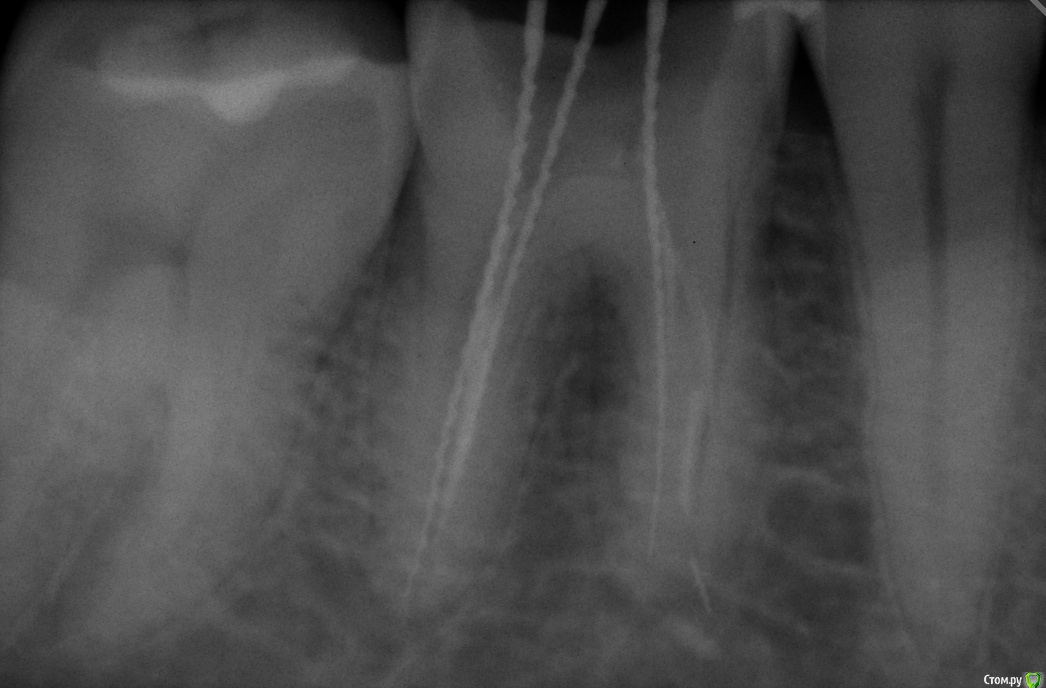

qweee89 Опубликовано 17 июля, 2015 Поделиться Опубликовано 17 июля, 2015 Дабы не плодить темы, с Вашего разрешения, напишу в этой ветке. Так как название как нельзя к стати...Итак, сегодня коллеги прислали снимок пациента с вопросом "Что делать?" Пац 33 года, 4.6 зуб сильная боль при накусывании( На сколько я понял что это пульпэкстрактор(Есть ли смысл слать пациента на микроскоп, или готовить его к апикальной хирургии? Ссылка на комментарий

inSight Опубликовано 17 июля, 2015 Поделиться Опубликовано 17 июля, 2015 тоже склоняюсь к пульпоэкстрактору, и (я чес слов перекрестился) кажется мне, что обломок на 2/3 не в зубе совсем. А коль так ,в процессе, есть вероятность его вытолкать , словить хирургу и лечить?! (вопрос больше к хирургам). Rg снимки еще есть? Ссылка на комментарий

qweee89 Опубликовано 17 июля, 2015 Поделиться Опубликовано 17 июля, 2015 тоже склоняюсь к пульпоэкстрактору, и (я чес слов перекрестился) кажется мне, что обломок на 2/3 не в зубе совсем. А коль так ,в процессе, есть вероятность его вытолкать , словить хирургу и лечить?! (вопрос больше к хирургам). Rg снимки еще естьТак и есть( За пределами корня. Как его готовить к апикальной хирургии? Чем пломбировать каналы? Ссылка на комментарий

St. Опубликовано 17 июля, 2015 Автор Поделиться Опубликовано 17 июля, 2015 Раз пульпэкстрактор сломан, лечили по поводу пульпита, правильно? а то мне расширение периодонталки мерещится..Металл, пусть и за пределами корня, сам по себе не может давать воспалительную реакцию и как следствие боль. Если болит, значит недомыли где-то. Что с проходимостью второго медиального(где по снимку инструмента нет и покоится отломок)?Я бы отмыла хорошо хлоркой, попыталась достать если видно в оптику. если нет - кальций на 14 дней. Возможно с заменами, если обострение будет. Ещё раз отмыть, хлоргексидин там тоже не лишним будет. и гутта с эпоксидкой. и наблюдать. Если обострение или периапикальные изменения прогрессируют - тогда хирургия. 2 Ссылка на комментарий

Audutor Опубликовано 17 июля, 2015 Поделиться Опубликовано 17 июля, 2015 Пломбировать лучше МТА, для возможной резекции в будущем это предпочтительней...По поводу болей согласен с St скорее проблема в неполной очистке.Вопрос к St что нам даст кальций? Ссылка на комментарий